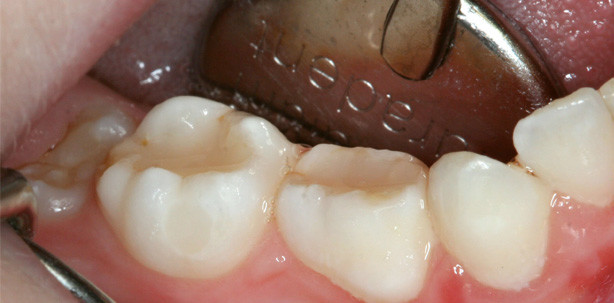

Behandlung eines neunjährigen Jungen mit Hämophilie A

Ein neunjähriger Junge mit schwerer Hämophilie A wies eine kariöse Läsion am oberen linken Milchmolaren auf (Abb. 1). Die Karies wurde zunächst mit einem konventionellen Rosenbohrer und final mit einem Polymerbohrer (PolyBur, P1, Komet Dental) vollständig exkaviert. Nach der Kavitätenrandpräparation wurde das Automatrix-Matrizensystem (AutoMatrix, DENTSPLY) appliziert (Abb. 2). Die Anwendung einer Matrize ist in jedem Fall zu empfehlen, da sich ansonsten das Bulkfüll-Material aufgrund seiner Viskosität an Stellen ausdehnt, die nicht zur eigentlichen Kontur der Füllung gehören. Als Adhäsiv kam ein selbstkonditionierendes All-in-One-Adhäsiv (Xeno V+, DENTSPLY) zur Anwendung, welches verblasen und lichtpolymerisiert wurde. Das Bulkfüll-Material SDR wurde direkt aus der Compula appliziert. Dabei ist es wichtig, dass die Metallkanüle auf dem approximalen Kavitätenboden aufgesetzt und sukzessive herausgezogen wird unter ständiger Förderung des dünnfließenden Materials. Die gesamte Kavität konnte auf einmal gefüllt und dann für 20 Sekunden lichtpolymerisiert werden. Da eine sichere Kontaminationskontrolle durch Watterollen und vierhändiges Arbeiten gewährleistet werden konnte, wurde auf Kofferdam verzichtet, was gerade im Hinblick auf die Anamnese des Jungen als Bluter von Vorteil war. Somit wurde eine mögliche Traumatisierung der Gingiva durch die Kofferdam-Klammer ausgeschlossen. Abschließend erfolgte die Ausarbeitung der Füllung mit Feinkorndiamanten (Abb. 3) und Politur (Enhance, DENTSPLY). Zum Zeitpunkt der Nachuntersuchung war der Milchzahn durch die natürliche Exfoliation nicht mehr in situ, sodass eine Kontrollaufnahme leider nicht vorliegt.